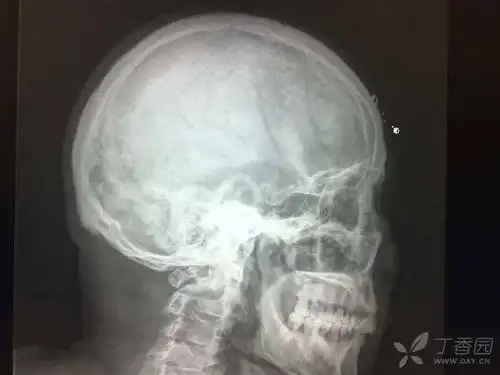

头侧位片显示患者牙合型为安氏Ⅱ类,轻度骨性Ⅲ类,上前牙唇倾,均角.

头颅侧位片可用于口腔正畸,正颌治疗前,中,后牙及颌骨相对位置的改变

头颅侧位片侧方位展现牙骨位置,通常拍摄曲面断层片的机器也可以拍摄